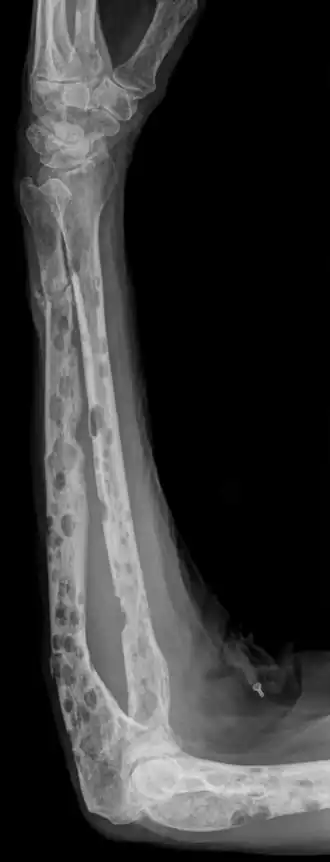

botafbraak in onderarm tgv Multipel myeloom | ||||

Als kwaadaardige plasmacellen het beenmerg innemen, kan de productie van rode bloedcellen, bloedplaatjes en witte bloedcellen in de vorm van neutrofielen in het gedrang komen. Hierdoor kunnen dan respectievelijk bloedarmoede, blauwe plekken en infecties optreden. De eerste symptomen zijn vaak echter botpijnen die ontstaan door zogenaamde osteolytische letsels. De kwaadaardige plasmacellen produceren namelijk OAF (Osteoclast Activating Factor), een eiwit dat aanzet tot botafbraak. Door deze botafbraak kan het calciumgehalte in het bloed verhoogd zijn (hypercalciëmie), wat aanleiding kan geven tot misselijkheid, verminderde eetlust, neurologische afwijkingen, hartklachten, jeukende ogen en obstipatie. Op termijn kunnen er ook nierbeschadigingen optreden ten gevolge van verhoogde eiwit- en calciumuitscheiding. De botten worden hierdoor broos en pijnlijk. Ook pathologische botbreuken en compressie van het ruggenmerg kan optreden bij deze patiënten. Bij de ziekte van Kahler worden veel defecte eiwitten (immunoglobulines) geproduceerd, die kunnen neerslaan in bijvoorbeeld de nieren. Nierfunctiestoornissen kunnen dan ook voorkomen bij de ziekte van Kahler. Indien er tevens amyloïd (onderdeel van de defecte eiwitten) afgezet wordt, kan men spreken van de ziekte amyloïdose.